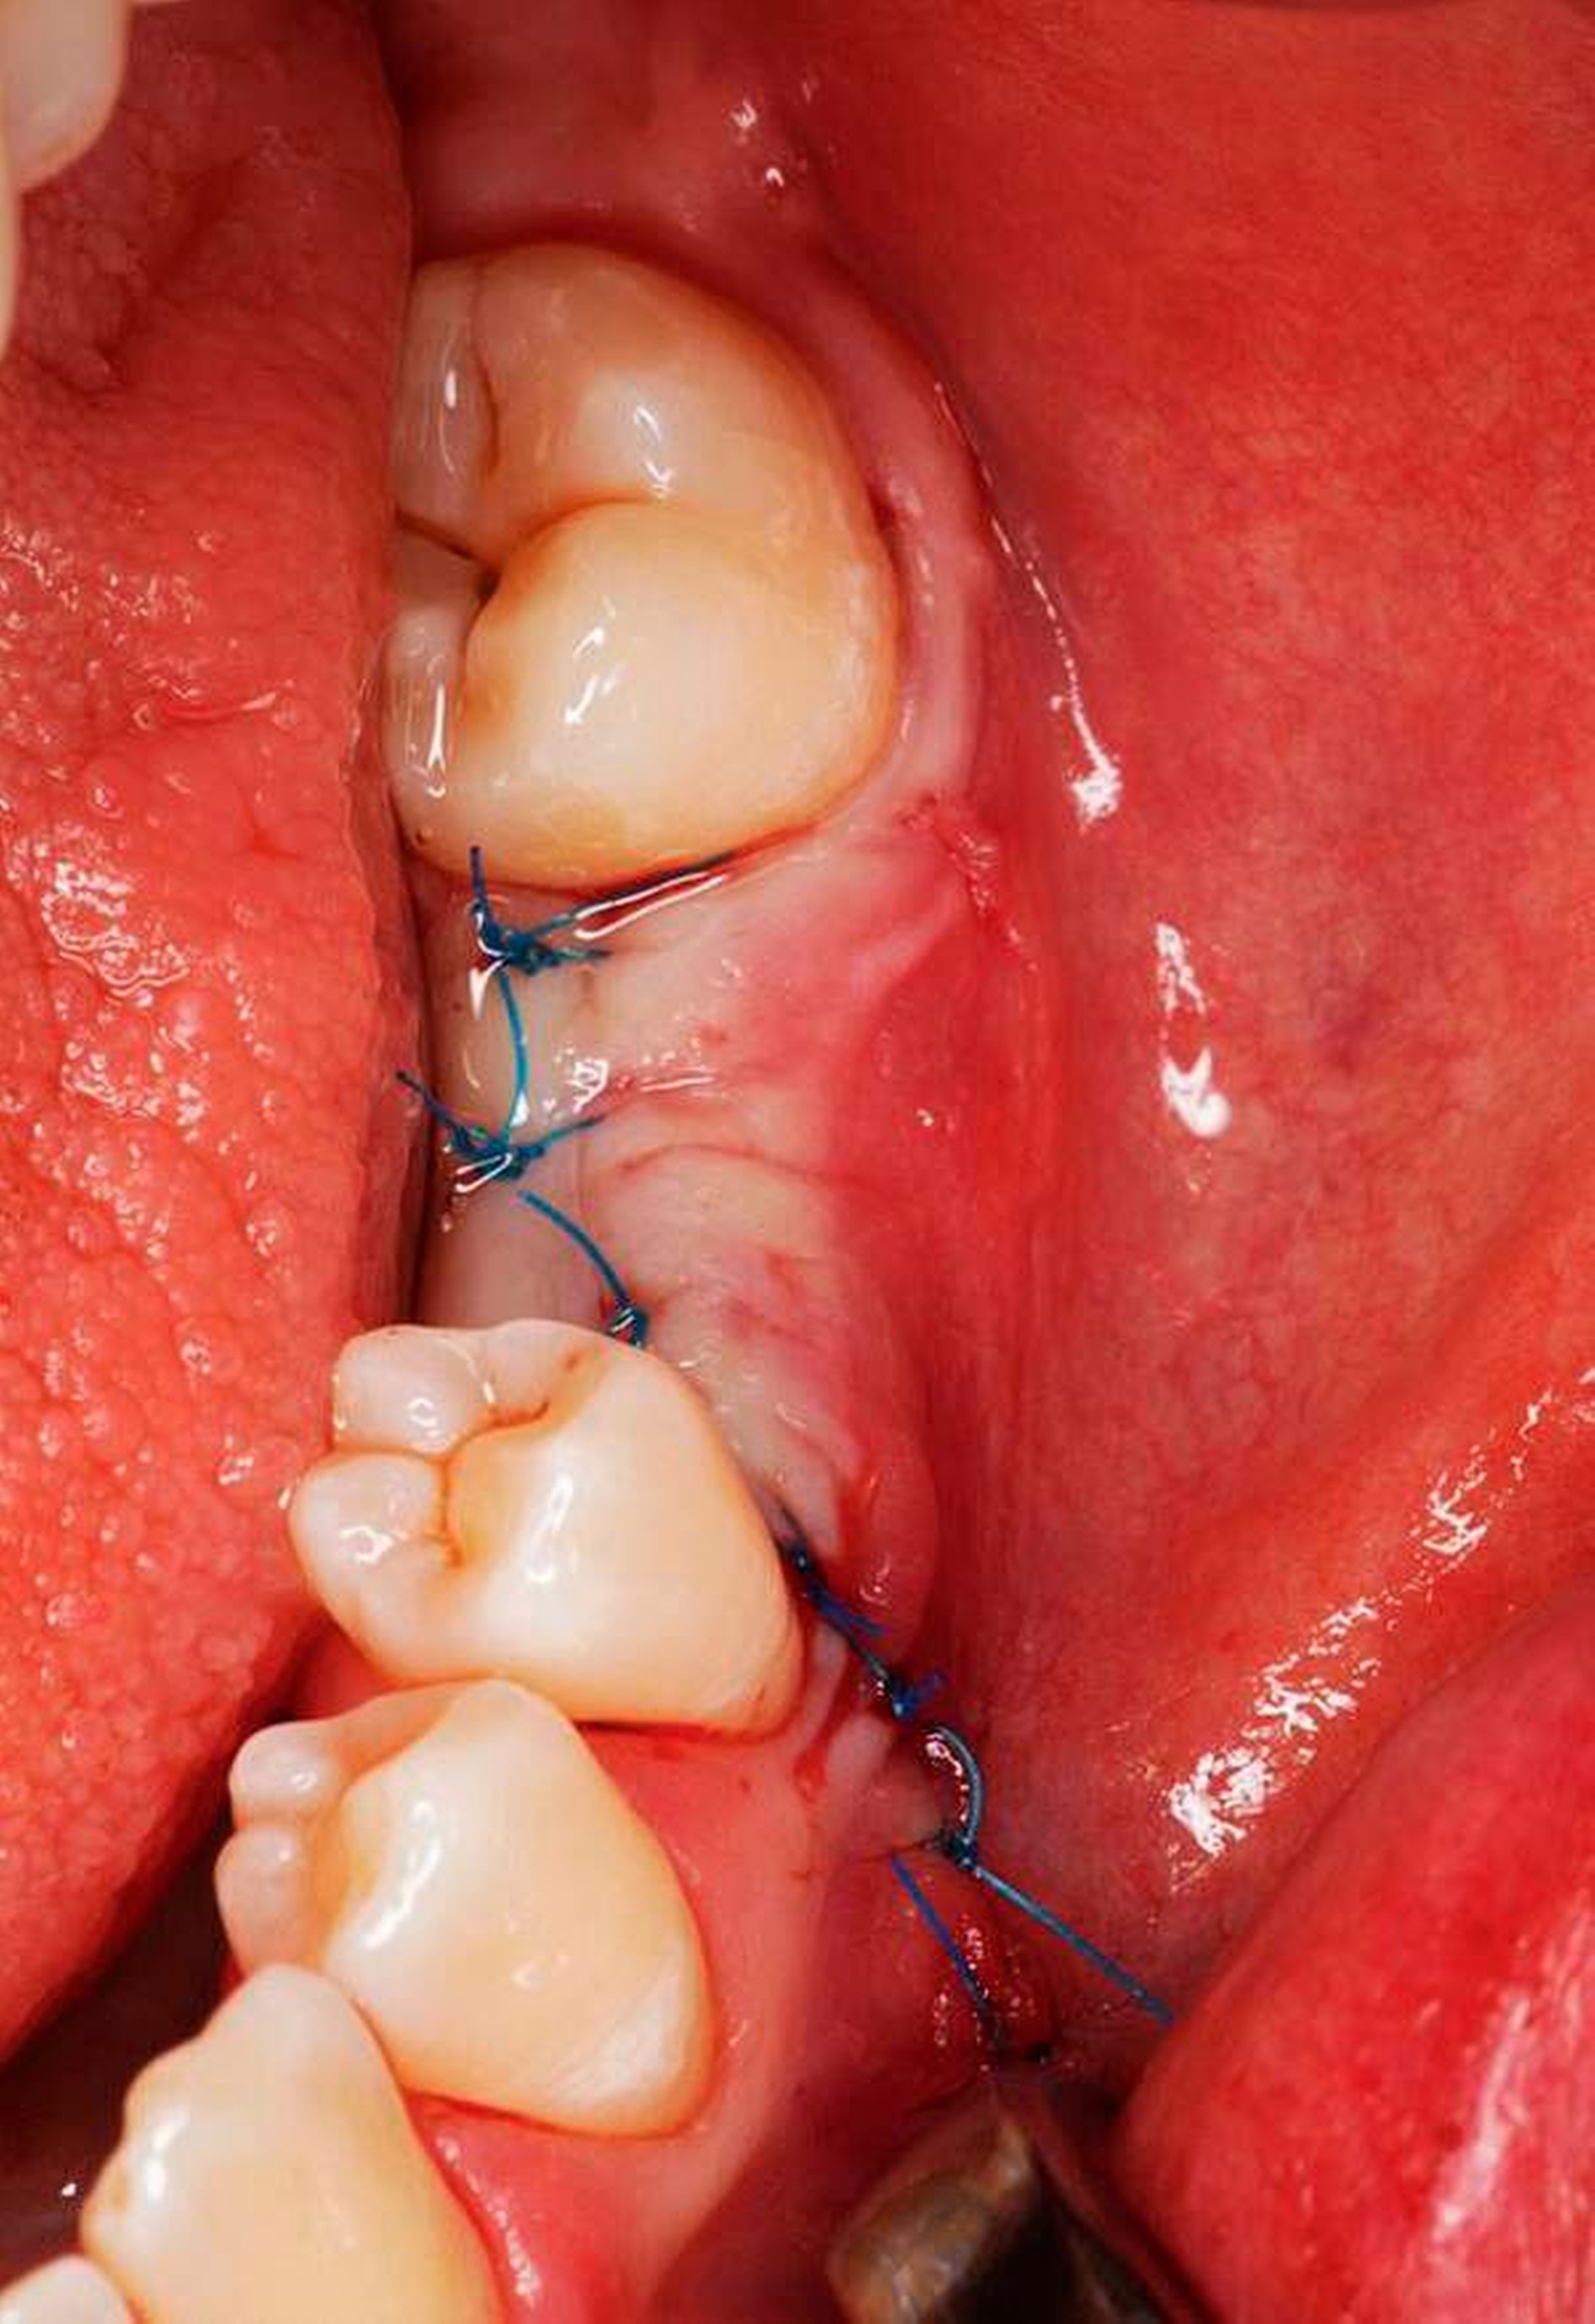

Auch radiologisch ließen sich keine Auffälligkeiten darstellen (Abbildung 1). Aufgrund der lang anhaltenden Persistenz und auf Wunsch der Patientin entschieden wir uns für eine chirurgische Inspektion mit Option auf Entfernung des Tumors. Analog zur Schnittführung der Weisheitszahnentfernung wurde das Gewebe Regio 36 marginal mit einer mesialen und distalen Entlastung eröffnet und ein Spaltlappen gebildet. Bis zur verdächtigen Raumforderung wurde stumpf mit der Schere präpariert (Abbildung 2), wobei sich die Läsion schließlich als abgekapselte Struktur darstellte, die sich sehr gut aus dem umliegenden Gewebe entfernen ließ. Das klinische Erscheinungsbild der Raumforderung entsprach am ehesten der eines Lipoms (Abbildung 3). Nach kompletter Entfernung der Raumforderung (Abbildung 4) wurde die Wunde mit Nähten speicheldicht verschlossen (Abbildung 5).